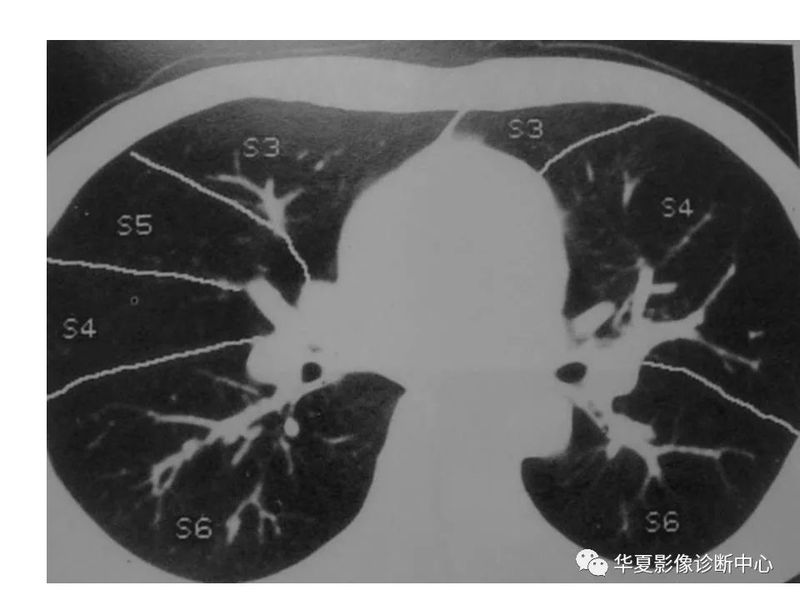

干货 | 汇总胸部CT读片扫盲知识,看懂胸部CT不再难